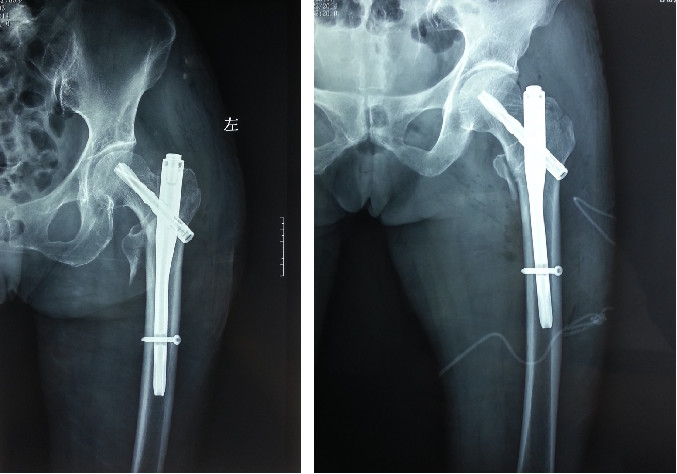

Un clou de plus petit diamètre (généralement 9 mm) peut être enfoncé sans dilatation.(au-dessus de l'extrémité caudale la plus épaisse du clou Gamma - 17 mm)

L'extrémité proximale du PFN a une cambrure approximative de 6 degrés, réduisant l'angle de valgus et éliminant le besoin d'une forte rétraction interne pendant la traction.

L'extrémité supérieure permet la mise en place de deux vis dans la tête fémorale, avec l'ajout d'une vis anti-rotation et d'un double appui de clou dans le col fémoral, ce qui augmente la résistance à la fatigue.

La distance entre le trou de verrouillage distal et l'extrémité distale du clou principal (extension conique) est plus longue, ce qui peut réduire la concentration de contraintes dans la tige fémorale.

Relativement moins de traumatismes.

Il s'agit d'une méthode de fixation intramédullaire mini-invasive avec une petite incision et un traumatisme minimal.

Le clou Gamma unit fermement le fémur supérieur et le col fémoral grâce à la combinaison du clou intramédullaire et de la vis de tension, et le clou intramédullaire est fixé par le clou autobloquant distal, qui empêche la rotation et le raccourcissement du déplacement et assure une fixation fiable.

Un appareil intégré idéal pour les fractures intertrochantériennes instables du fémur.